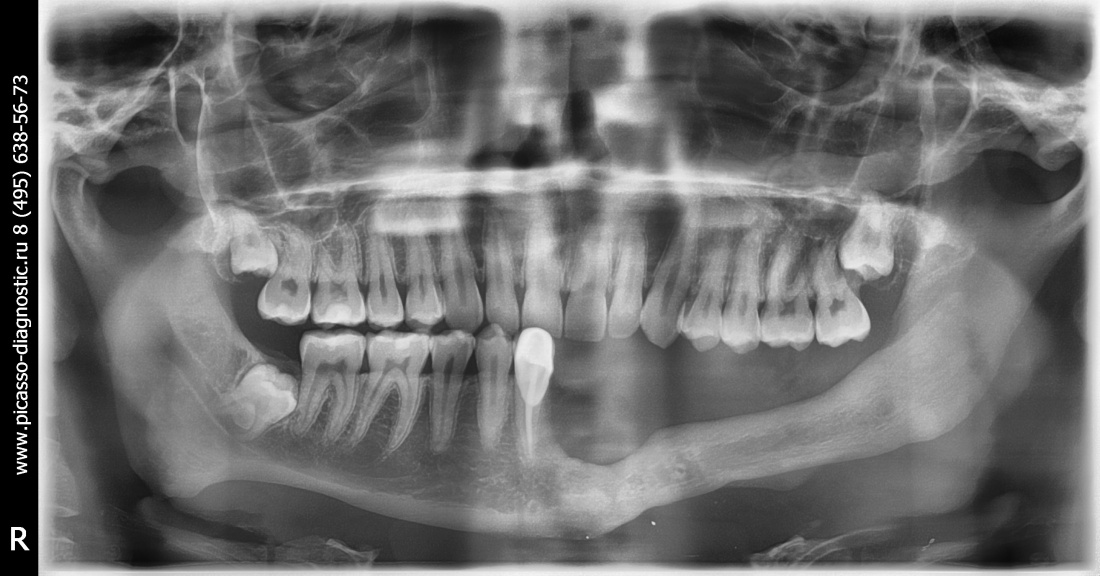

Не нужно расстраиваться! Базальная имплантация — это поправимо.